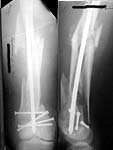

A male 31 y.o. addmitted to our unit today with the subject (see attachment). Injured in a car accident 1 month ago, since that he has been at bed traction. Other fractures are minor - undisplaced pubic rami and distal ulna.

What is your opinion about optimal program here? Is closed nailing a good option here? Articular part of condyles looks fine, but the lateral one seems to be too small and comminuted. Or external fixation as definitive method? Or open the fracture at least distally, fix condyles then nail?

Of course the only radiograms both the view of the femur (AP and LL) are not enough in order to assess the condyles. So I think a TAC of the knee could be useful.

A CT and knee xrays would help identify lateral condyle comminution and/or a "hoffa fragment" of the posterior condyle. I am concerned that the lateral cortex is not sufficient to give purchase for a retrograde IMN. blocking screws could improve this as a possibility.

Yesterday antegrade closed nailing was performed (UFN 10 mm). Two cancellows screws added to fix the lateral condyle. The surgery was not too easy, and extension of condylar part i failed to reduce completely. The shaft looks even more ugly. The patient left for a couple of days in 90/90 position. Comments/opinions/advices are welcome.